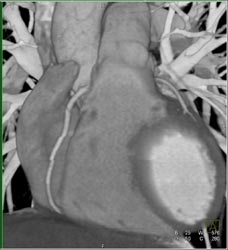

Step Off Due to Incorrect Phase of Reconstruction-see Sequence of Images